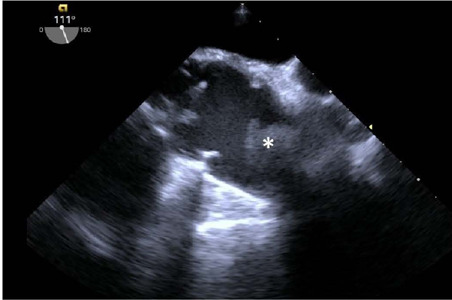

A 58-year-old man, who has undergone ascending aorta replacement, started to complain of pain in the lower limbs, shortness of breath, and progressive fatigue a few months after surgery. Transthoracic and transesophageal Doppler echocardiographies revealed a diseased bicuspid aortic valve and a subocclusive mass in the ascending aorta. Thoracic computed tomography angiography confirmed the presence of a subocclusive mass, pseudoaneurysm formation, and a distorted shape of the Dacron® graft. The patient underwent urgent surgery to remove the mass, which appeared to be a thrombus, and aortic valve and ascending aorta replacement. Kinking of vascular graft has been reported including surgical techniques to correct the excessive length to avoid gradients and guarantee laminar flow. When kinking is severe, high gradients and hemolysis can be detected. However, thrombus formation in the ascending aorta segment is less likely, due to the high blood velocity flow. Therefore, several concurrent causes should be considered. In this case, the most probable explanation for thrombus formation was kinking of a too long Dacron® graft, combined with extrinsic compression effect of the graft by the pseudoaneurysm at the anastomosis site and anomalous flow directed from the diseased bicuspid aortic valve. Various grades of Dacron® graft kinking might occur following ascending aorta replacement and undiagnosed at follow-up especially if resulting in mild symptoms, thus, careful visual and echocardiography evaluation should be done at the end of surgery. Finally, distorted Dacron® graft might trigger thrombus formation when inflammation and coagulation processes are set off during bacteria or viral infection.

Abstract Image